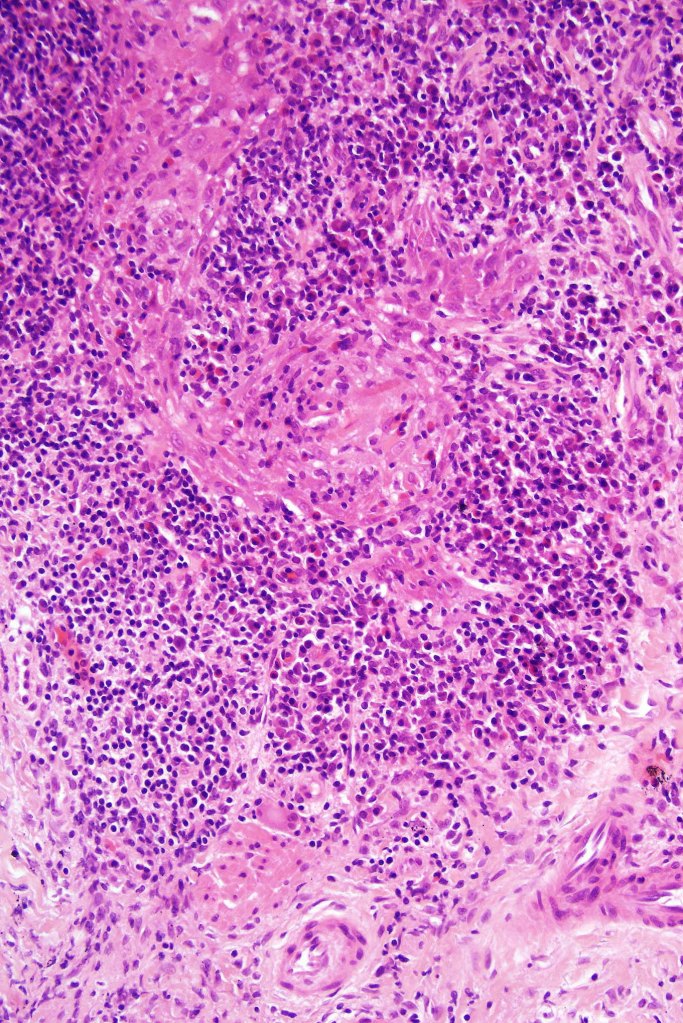

Histological features

•Follicular infiltration by atypical lymphocytes & Sézary cells

•Eosinophils sometimes conspicuous (eosinophilic folliculitis-like appearance)

•Granulomatous inflammation secondary to follicular destruction

•Large cell transformation occasionally present